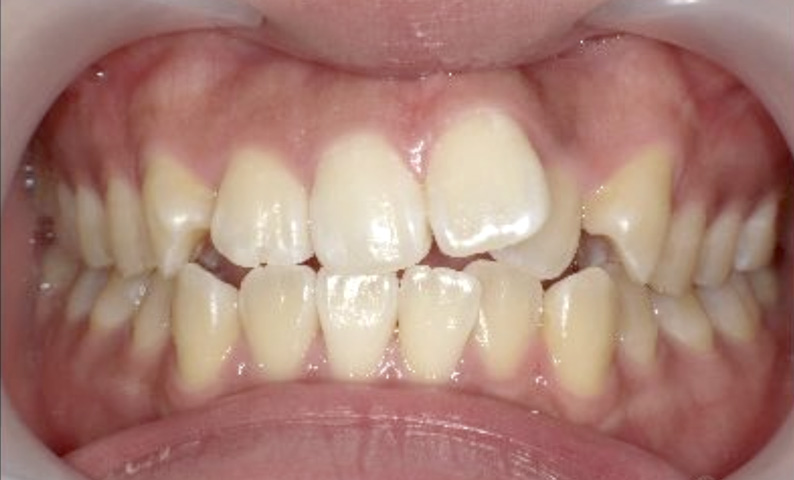

症例_022 上下顎の部分矯正

治療期間:7ヶ月金額:54万円+税女性前歯のガタガタ八重歯一部反対咬合

| Before | After |